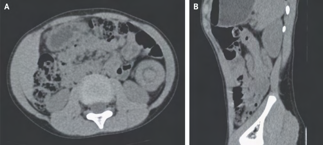

Recent studies indicate that Generative Pre-trained Transformer 4 with Vision (GPT-4V) outperforms human physicians in medical challenge tasks. However, these evaluations primarily focused on the accuracy of multi-choice questions alone. Our study extends the current scope by conducting a comprehensive analysis of GPT-4V's rationales of image comprehension, recall of medical knowledge, and step-by-step multimodal reasoning when solving New England Journal of Medicine (NEJM) Image Challenges - an imaging quiz designed to test the knowledge and diagnostic capabilities of medical professionals. Evaluation results confirmed that GPT-4V outperforms human physicians regarding multi-choice accuracy (88.0% vs. 77.0%, p=0.034). GPT-4V also performs well in cases where physicians incorrectly answer, with over 80% accuracy. However, we discovered that GPT-4V frequently presents flawed rationales in cases where it makes the correct final choices (27.3%), most prominent in image comprehension (21.6%). Regardless of GPT-4V's high accuracy in multi-choice questions, our findings emphasize the necessity for further in-depth evaluations of its rationales before integrating such models into clinical workflows.